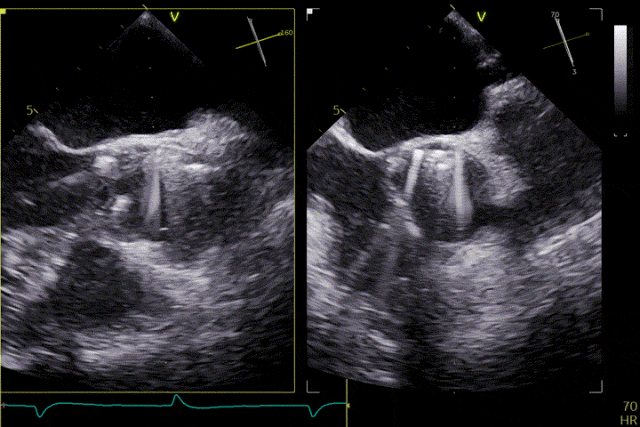

術前超聲

輸送器跨瓣

打開定位件

定位件入竇

瓣膜釋放